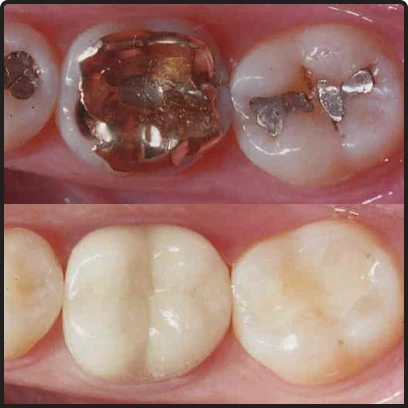

Safe Amalgam Filling Removal

Many older “Silver” fillings contain up to 50% elemental mercury. These fillings can, over time, expand, causing microfractures in your teeth. or release trace amounts of mercury vapor. Replacing is a step toward holistic health.

- Prevents the inhalation or ingestion of toxic mercury vapors during the removal process.

- Replaces expanding metal with biocompatible materials.

- Supports a holistic lifestyle by removing heavy metals from your mouth.

S.M.A.R.T. Protocol

In Smile Makeover Playa del Carmen we follow the Safe Mercury Amalgam Removal Technique (SMART) as established by the IAOMT.

We use specialized equipment using the SMART Process.

- SMART Protocol Service

- Specialized safety barriers, oxygen delivery, and filtration